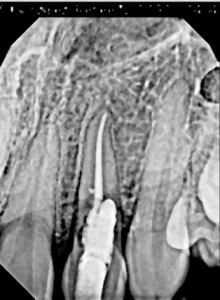

This video demonstrates immediate implant placement in the esthetic zone following atraumatic extraction of a lateral incisor. Emphasis is placed on preserving the hard and soft tissue architecture critical for predictable esthetic outcomes.

The procedure is presented step by step, including minimally traumatic extraction techniques, immediate implant placement, and fabrication and placement of a customized healing abutment to support peri-implant soft tissue contours. Clinical principles for maintaining papillae, controlling the emergence profile, and optimizing soft tissue healing are highlighted.